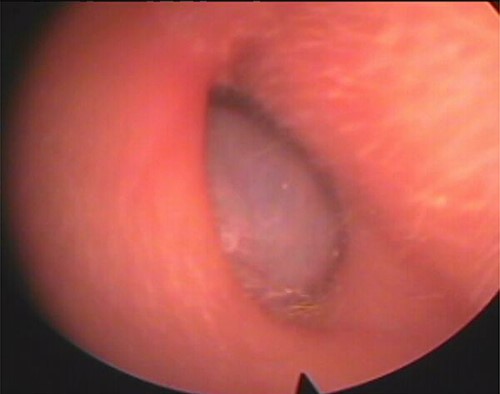

Our patient was a 40-year-old female, with unremarkable disease history, who presented with a fullness of the right ear for 6 months which was associated with progressive hypoacusis and intermittent ipsilateral tinnitus. The clinical examination showed a mass in the right external auditory canal, attached to the posterosuperior wall, which was smooth, pink, firm, mobile, well limited and hemorrhagic on contact (Fig. 1). Weber and Rinne tuning fork tests were negative and right-lateralized, respectively. Preoperative pure tone audiometry revealed an average right conductive hearing loss of 37.5 dB. Imaging based on computed tomography (CT) scan showed a mass occupying the outer two-thirds of the right external auditory canal, measuring 17 mm, well limited, with regular contours. The tissue radio density measured was 61 HU with erosion of the middle ear (Fig. 2).